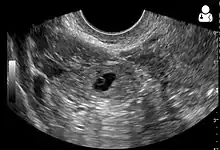

An ultrasound showing a gestational sac with fetal heart in the fallopian tube has a very high specificity of ectopic pregnancy. Transvaginal ultrasonography has a sensitivity of at least 90% for ectopic pregnancy.[4] The diagnostic ultrasonographic finding in ectopic pregnancy is an adnexal mass that moves separately from the ovary. In around 60% of cases, it is an inhomogeneous or a noncystic adnexal mass sometimes known as the "blob sign". It is generally spherical, but a more tubular appearance may be seen in case of hematosalpinx. This sign has been estimated to have a sensitivity of 84% and specificity of 99% in diagnosing ectopic pregnancy.[4] In the study estimating these values, the blob sign had a positive predictive value of 96% and a negative predictive value of 95%.[4] The visualization of an empty extrauterine gestational sac is sometimes known as the "bagel sign", and is present in around 20% of cases.[4] In another 20% of cases, there is visualization of a gestational sac containing a yolk sac or an embryo.[4] Ectopic pregnancies where there is visualization of cardiac activity are sometimes termed "viable ectopic".[4]

Ultrasound image showing an ectopic pregnancy where a gestational sac and fetus has been formed.